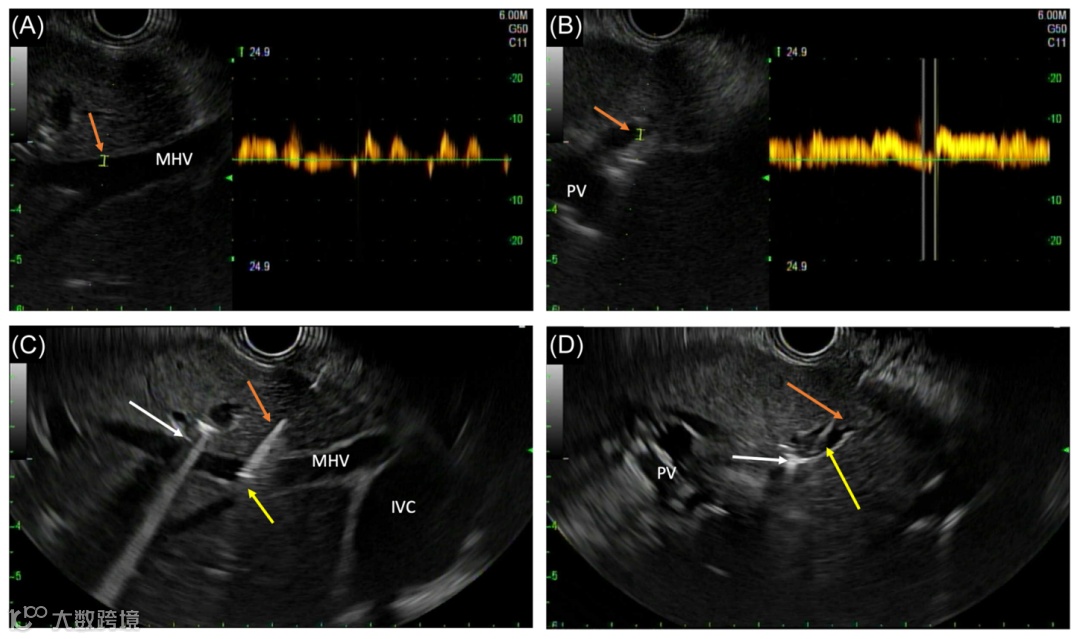

超声内镜下观察肝脏和血管结构

本研究共纳入18名患者接受EUS-PPG检查,其中17人操作成功,且无并发症发生。通过测量,5名患者存在临床显著性门静脉高压(根据内镜结果诊断)。此外,15名患者同时进行了EUS引导下的肝脏活检,均成功提供了诊断性的组织学信息,EUS-PPG测量使得17例患者的临床管理方案发生了变化,其中包括原计划接受手术的患者,被转诊进行非手术治疗;有5例患者也因EUS引导下的肝穿活检,确认了肝硬化的诊断。研究表明,EUS-PPG在改善肝病患者管理方面具有潜力,可在实践中为疑似或确诊肝病的患者提供具有治疗意义的指导。